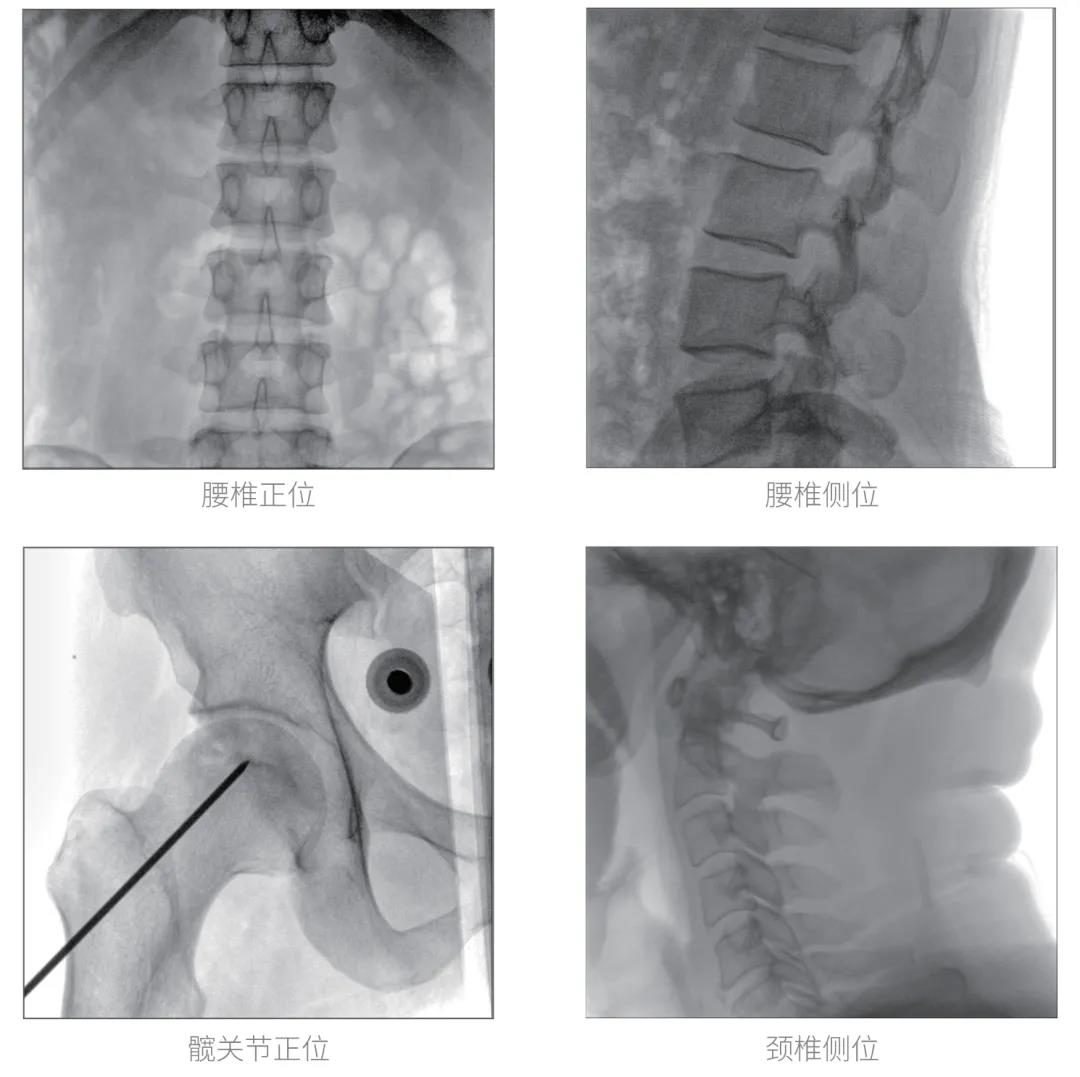

經(jīng)過認(rèn)真詳盡的設(shè)備審核驗(yàn)收,“慧瞳”正式投入使用,普愛醫(yī)療一體化平板C形臂采取的動(dòng)態(tài)平板探測器和智能圖像處理技術(shù),讓臨床圖像更加清晰。

普愛醫(yī)療一體化平板C形臂“慧瞳”采用小巧緊湊的一體化機(jī)架設(shè)計(jì),配合高性能的動(dòng)態(tài)平板探測器,移動(dòng)靈活,成像清晰,是各級(jí)醫(yī)院開展骨科及其相關(guān)外科手術(shù)的科室使用的理想設(shè)備。

智能化實(shí)時(shí)圖像處理技術(shù),自動(dòng)分析圖像并進(jìn)行增強(qiáng)處理,減少臨床應(yīng)用中處理圖像時(shí)的繁瑣操作,快速提供優(yōu)質(zhì)圖像方便完成臨床工作。